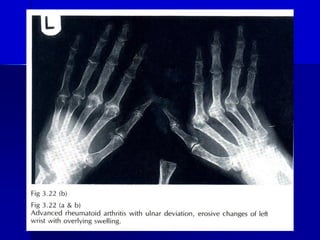

◼ 7. X Quang khôùp :

- Giai ñoaïn ñaàu : söng moâ meàm , traøn

dòch khôùp , loaõng xöông gaàn khôùp

- Gñ sau : suïn khôùp bò huûy , bôø xöông

nham nhôû , loeùt xöông , truïc khôùp leäch

◼ 7. XQ thay ñoåi : xöông coå tay , baøn tay : moøn

xöông , maát voâi